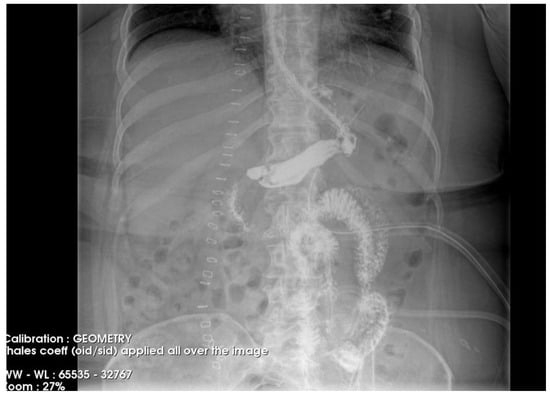

To gain a more comprehensive understanding of the patient’s condition, a contrast-enhanced abdominopelvic computer tomography (CT) scan was performed. Imaging revealed a reduced gastric volume with the nasogastric tube in place, previously positioned with its distal tip at the subcardial region (Figure 1a,b). In the gastric fornix, two parietal defects were observed, measuring 13 mm (on the posterior wall) and 3 mm (on the anterior wall), with the passage of orally administered contrast substance into the fat of the gastro-splenic ligament. Near the greater curvature of the stomach, a few gas bubbles were present in the omental fat. Further investigations were carried out, including an endoscopic examination, which revealed the esophagus with a 20 mm lumen and tertiary contractions. Additionally, a highly intense pneumatosis was observed throughout the entire colonic frame. The contrast agent administered during the procedure was later detected at the level of the left colon, further guiding the diagnostic process. Following this thorough clinical and paraclinical evaluation, the diagnosis of a high gastric fistula secondary to a gastric sleeve procedure was confirmed.

Figure 1.

(a,b) Abdominal computer tomography (coronal and axial view)—parietal defects are observed with the presence of the contrast substance in abdominal cavity.